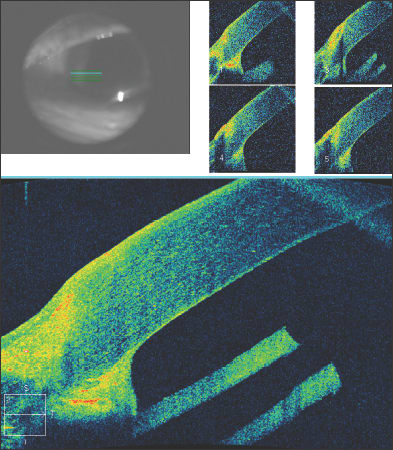

The results of surgical interventions can also be documented, including the position of Descemet's stripping endothelial keratoplasty buttons, glaucoma tube shunts or intraocular lenses. After penetrating keratoplasty, the graft-host interface can be evaluated as seen in this patient with a traumatic corneal laceration, resulting in an emergent penetrating keratoplasty and suboptimal graft-host alignment (Figure 7). Filtering blebs after trabeculectomy can be evaluated, and subconjunctival filtration can be demonstrated (Figure 8).

After DSEK, the position and apposition of the donor endothelial button can be evaluated. In Figure 9a, the endothelial button can be seen to be non-adherent to the corneal stroma, with associated epithelial bullae. After several months, the endothelial button has become fully adherent, and the epithelial fluid has resolved (Figure 9b). In Figure 10, we see a patient who has undergone combined penetrating keratoplasty and tube shunt implantation, and the tube position, while somewhat anterior, is confirmed to be free of corneal touch. The graft-host junction is visualized and the corneal stroma and endothelium anterior to the tube tip appear normal.

Figure 9. Shortly following Descemet's stripping endothelial keratoplasty, the endothelial button can be seen to be non-adherent to the corneal stroma, with associated epithelial bullae (Fig. 9a, above). After several months, the endothelial button has become fully adherent, and the epithelial fluid has resolved (Fig. 9b, below).

Figure 10. Anterior segment OCT of a patient who has undergone combined penetrating keratoplasty and tube shunt implantation. The tube position, while somewhat anterior, is confirmed to be free of corneal touch.